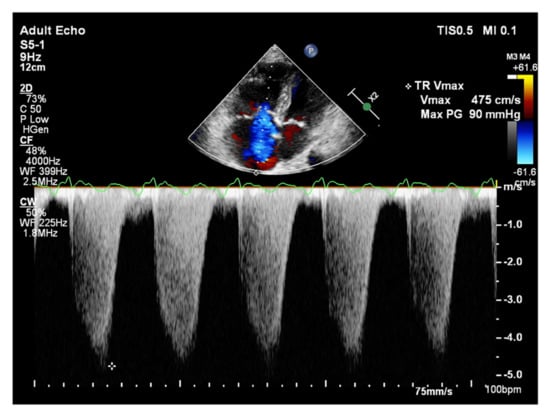

It is believed that if there is no RV outflow tract stenosis, the right ventricular systolic pressure (RVSP) is equal to the pulmonary artery systolic pressure (PASP) [70]. In everyday practice, the calculation of PASP is based on a simplified Bernoulli equation applied to peak tricuspid regurgitation velocity (TRV). TRV should be measured in several views, aiming at the best image quality and maximum velocity in continuous-wave Doppler and avoiding excessive gain and artifacts (Figure 12 and Figure 13). According to the equation, PASP = 4 (TRV)2 + RAP [71,72]. In addition, based on the measurements of end-diastolic pulmonary regurgitant return wave velocity (PRVend), it is possible to estimate pulmonary artery diastolic pressure (PADP) using the PADP = 4 (PRVend)2 + RAP formula [73]. On the other hand, PASP and PADP values can be used to calculate approximations of mean pulmonary artery pressure (mPAP) using the mPAP = 1/3 (PASP) + 2/3 (PADP) formula [74]. Several other formulas for calculating mPAP can be found in the literature. Chemla et al. developed another method to calculate mPAP, according to the formula mPAP = 0.61 × PASP + 2 mmHg [75].

Figure 13.

Doppler assessment of tricuspid regurgitant velocity (TRV). Differential rate of tricuspid regurgitation wave jets in atrial fibrillation. TTE, 4CH view. TTE: transthoracic echocardiography; 4CH: four-chamber.